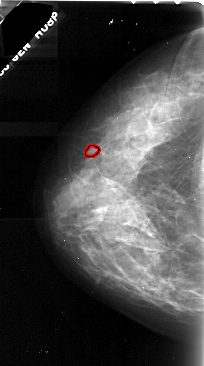

A_1047_1.LEFT_MLO

LEFT_MLO LINES 5521 PIXELS_PER_LINE 2971 BITS_PER_PIXEL 16 RESOLUTION 42 OVERLAY

FILE: A_1047_1.LEFT_MLO.OVERLAY

TOTAL_ABNORMALITIES 1

ABNORMALITY 1

LESION_TYPE CALCIFICATION TYPE PLEOMORPHIC DISTRIBUTION CLUSTERED

ASSESSMENT 4

SUBTLETY 2

PATHOLOGY MALIGNANT

TOTAL_OUTLINES 1

BOUNDARY